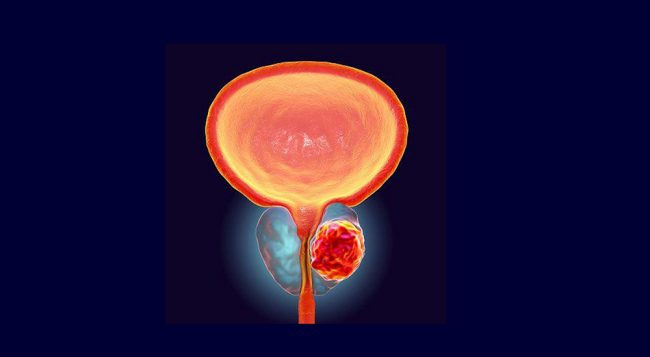

खुट्टामा देखिने यी ५ लक्षण डायबिटीजको लक्षण हुन सक्छ!

काठमाडौं। डायबिटीज एक जीवनशैली रोग हो जसको कारण आज धेरै संख्यामा मानिसहरू पीडित छन्। बदलिँदो खानपान र जीवनशैलीका कारण आज सुगरका बिरामीको संख्या ह्वात्तै बढेको छ ।

मधुमेहको समस्या सामान्यतया हाम्रो शरीरले ग्लुकोज नियन्त्रण गर्न नसक्दा देखापर्छ। हाम्रो शरीरलाई ऊर्जा प्रदान गर्ने काम ग्लुकोजले गर्छ। जुन हामीले खानाबाट प्राप्त गर्छौं । जब हाम्रो शरीरले यो ग्लुकोजलाई ऊर्जामा परिणत गर्न सक्दैन, यसले मधुमेह निम्त्याउँछ।

कुनै पनि रोगको जोखिम कम गर्न, यसको प्रारम्भिक चरणहरूमा पहिचान गर्न महत्त्वपूर्ण छ। तर, सुरुमा मधुमेह पहिचान गर्न निकै गाह्रो हुन्छ, किनभने प्रायः सुरुमा कुनै गम्भीर लक्षणहरू देखिँदैनन्।

हामी तपाईलाई खुट्टामा देखिने केहि लक्षणहरु बताउन गइरहेका छौँ जसले मधुमेहको स्पष्ट संकेत गर्छ । यदि तपाईंले समयमै संकेतहरू बुझ्नुभयो भने, तपाईंले यो रोग नियन्त्रण गर्न सक्नुहुन्छ। जानौं खुट्टामा देखिने मधुमेहका ५ लक्षणहरू।

खुट्टा सुन्निनेः यदि तपाईको खुट्टा बिना कारण सुन्निएको छ भने यो मधुमेहको गम्भीर लक्षण हुन सक्छ। यसको साथमा, यदि तपाइँको खुट्टा र घुँडा मुनिको भाग सुन्निएको छ भने मधुमेहको संकेत हुन सक्छ। मधुमेह रोगीको शरीरमा रक्तसञ्चार ठीक नहुँदा यस्तो समस्या आउन सक्छ । चिकित्सक संग सल्लाह लिन सक्नुहुनेछ।

लगातार खुट्टा सुन्निनेः यदि तपाई लगातार आफ्नो खुट्टा सुन्निने समस्याको सामना गरिरहनु भएको छ भने, यो तपाईको शरीरमा ग्लुकोजको मात्रा बढेको संकेत हुन सक्छ।

डायबिटीज रोगीहरूले प्रायः आफ्नो खुट्टामा झुन्झने समस्याको सामना गर्छन्। यसको पछाडिको कारण यो हो कि मधुमेहमा हाम्रो रगतमा चिनीको मात्रा बढ्छ जसले हाम्रो शरीरको नसालाई क्षति पुर्याउँछ। जसका कारण खुट्टामा यस्तो समस्या आउन सक्छ ।

सुख्खा छालाः डायबिटीजका रोगीहरुको खुट्टाको छाला प्रायः सुख्खा र निर्जीव हुन थाल्छ । यसका साथसाथै यदि तपाइँ आफ्नो खुट्टाको छालामा सुख्खापन र चिलाउने जस्ता समस्याहरू सामना गर्दै हुनुहुन्छ भने, यो मधुमेहको लक्षण हुन सक्छ। वास्तवमा मधुमेहका कारण छालामा पोषकतत्व राम्ररी पुग्दैन जसले गर्दा यो समस्या हुन्छ ।

खुट्टामा दुखाइः यदि तपाईको खुट्टामा एक्कासी दुखाइ र क्र्याम्प छ भने, यो मधुमेहको लक्षण हुन सक्छ। यसबाहेक राती सुत्नुअघि यस्तो दुखाइ भएमा मधुमेहका कारण हुने सम्भावना धेरै हुन्छ । यदि तपाई पनि यस्तो समस्याबाट ग्रसित हुनुहुन्छ भने ढिलो नगरी चिकित्सकको सल्लाह लिनुपर्छ ।

खुट्टाको घाउ छिट्टै निको हुँदैनः मधुमेहको सबैभन्दा महत्त्वपूर्ण लक्षण भनेको यसबाट पीडित व्यक्तिको शरीरमा लागेको घाउ सजिलै निको नहुनु हो। यदि तपाईको खुट्टामा चोट लागेको छ र निको हुन धेरै समय लागेको छ भने तपाई मधुमेहको शिकार हुनुभएको प्रष्ट संकेत हो ।